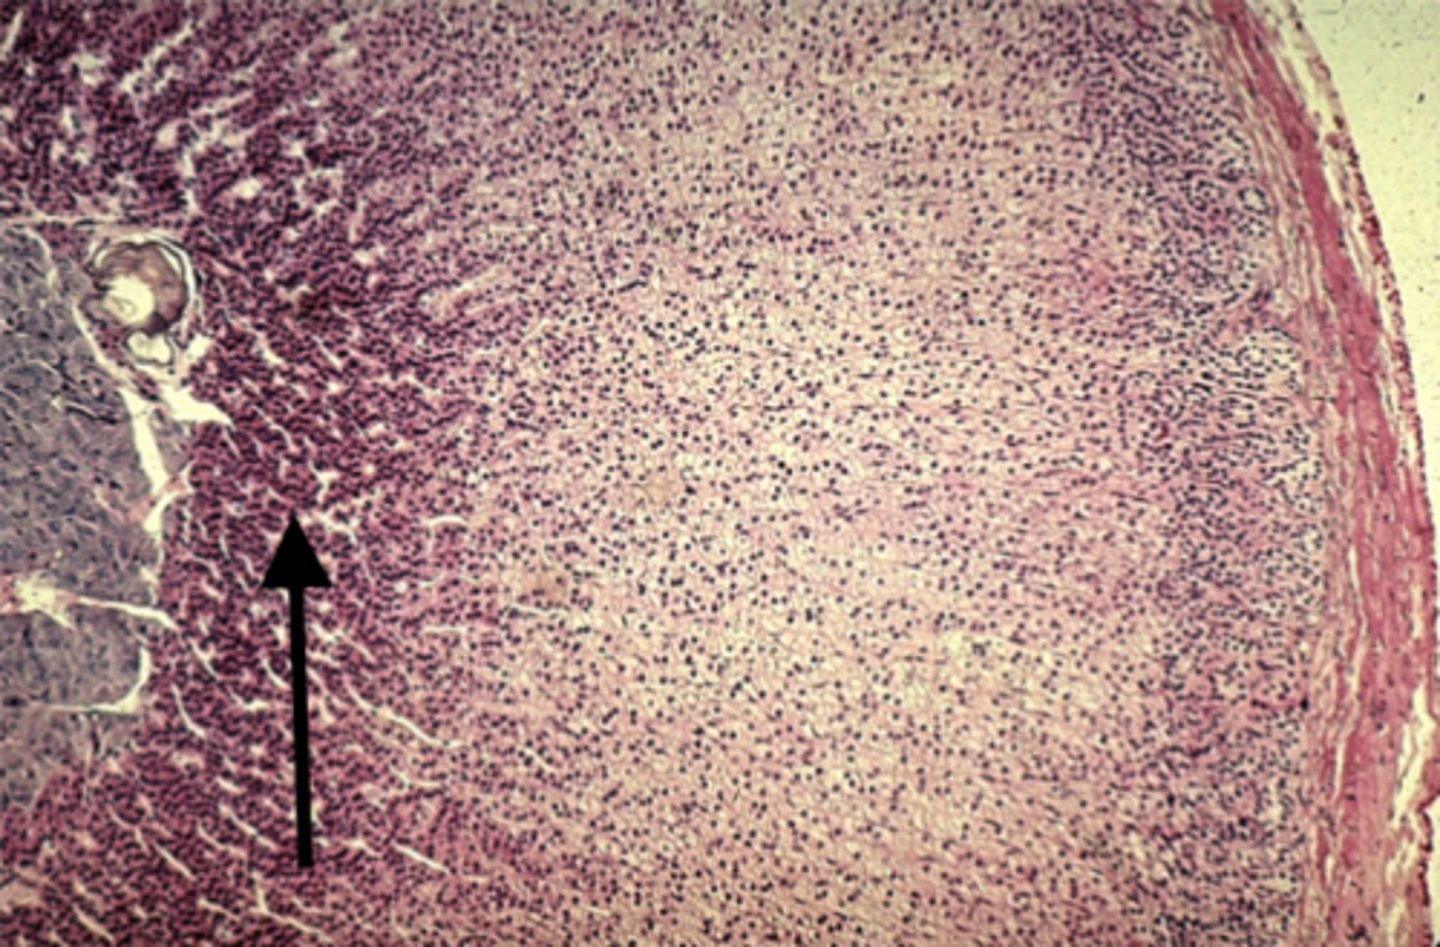

Adrenal gland

what is this?

Zona fasciculata

what is this pointing to?

Zona reticularis

what is this pointing to?

medulla

what is this pointing to?

Cortisol

Zona fasciculata secretes

Aldosterone

Zona glomerulosa secretes

Androgens

Zona reticularis secretes

Epinephrine

What hormone does the adrenal medulla secrete?